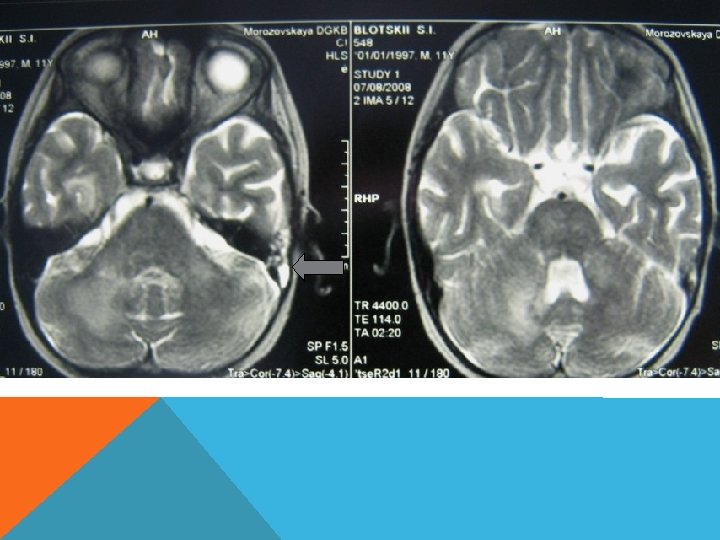

ГЕРПЕТИЧЕСКИЙ ЭНЦЕФАЛИТ ОЧАГИ ПОРАЖ ЕНИЯ ВЕЩЕС ТВА МОЗГА НА МРТ